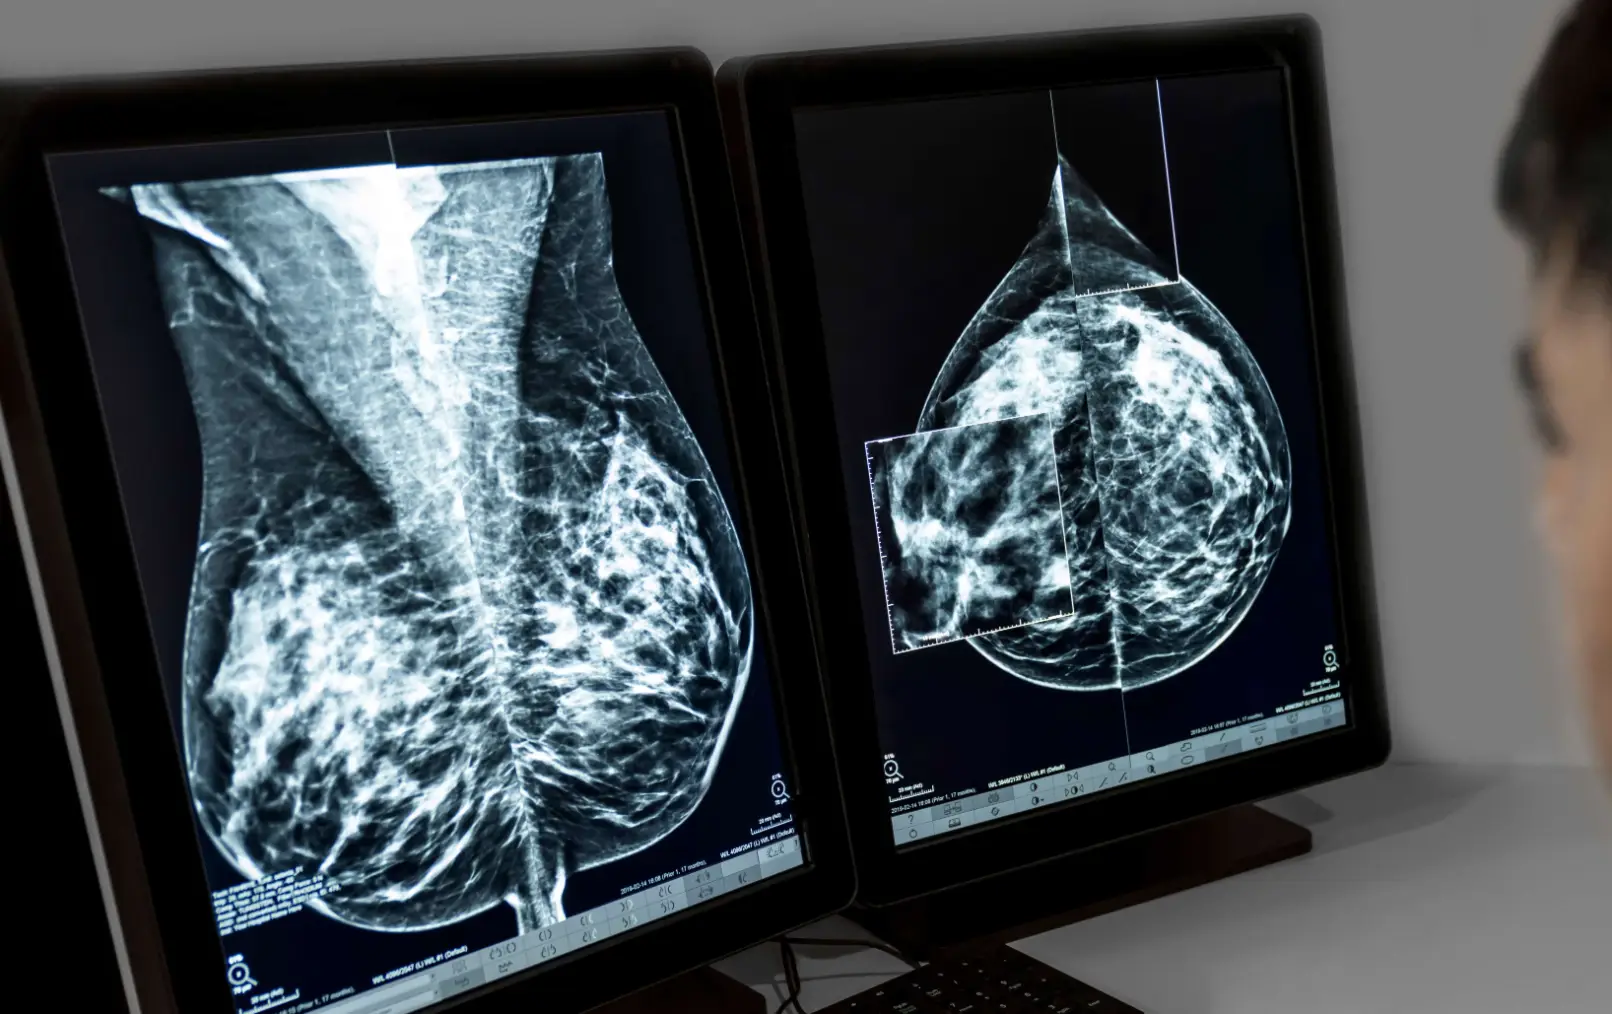

A mammogram is a non-invasive high resolution, low-energy, digital x-ray picture that plays an essential role in the early detection and screening of breast cancer. Also called mastography, the goal of a mammography is to detect the characteristics of masses or microcalcifications.

The procedure involves positioning the patient upright, with one breast at a time carefully situated between two x-ray plates. These plates are then adjusted gradually to compress the breast tissue, ensuring optimal image quality. Two images are captured for each breast: one from top to bottom and another from side to side.

The images will be interpreted by a radiologist who will share the results with your referring doctor. It is suggested to schedule a follow-up appointment with your doctor to ensure that a clear explanation of the results is provided.